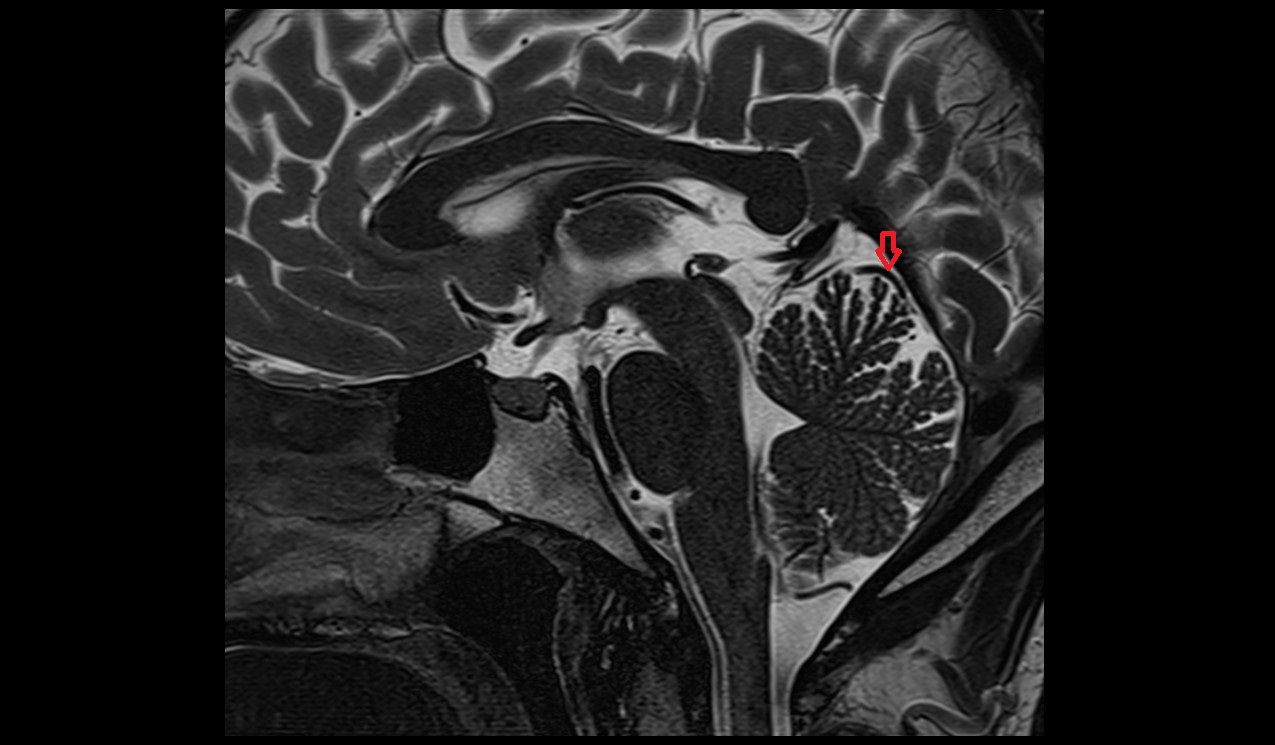

- Pineal gland